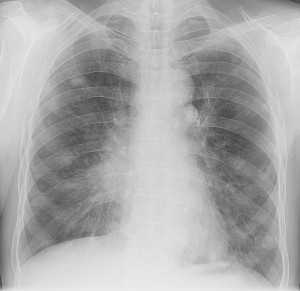

Диагностику заболевания осуществляют врачи-онкологи, к которым больных обычно направляют травматологи и ортопеды. Клинические симптомы при хондросаркоме неспецифичны, поэтому диагноз выставляется на основании дополнительных исследований. При центральных хондросаркомах на рентгеновских снимках обнаруживается очаг деструкции неправильной формы с нечеткими очертаниями, обычно расположенный в метадиафизе. Иногда опухоль выглядит крапчатой из-за мелких очажков обызвествления. Кость вокруг очага вздута.

При периферических хондросаркомах на рентгенограммах выявляется контрастное образование бугристой формы с нечеткими контурами, расположенное на наружной поверхности кости. В переходной зоне между нормальной костью и измененной опухолевой тканью отмечается неравномерное уплотнение. Кортикальный слой кости в этой зоне неровный. Как и при центральной хондросаркоме, может выявляться крапчатость из-за участков обызвествления.

Для уточнения диагноза выполняют трепанобиопсию кости. Забор материала производится из нескольких участков опухоли. В процессе гистологического исследования определяется степень злокачественности хондросаркомы. Как правило, перечисленных исследований достаточно для точной диагностики. В отдельных случаях могут понадобиться дополнительные методы: МРТ кости, компьютерная томография и остеосцинтиграфия. Для выявления метастазов в легких пациентам с хондросаркомой назначается рентгенография грудной клетки.

Рентген грудной клетки. У некоторых людей с хондросаркомами, раковая опухоль может распространяться в лёгкие. Рентген грудной клетки обычно делают для того, чтобы проверить так это или нет.